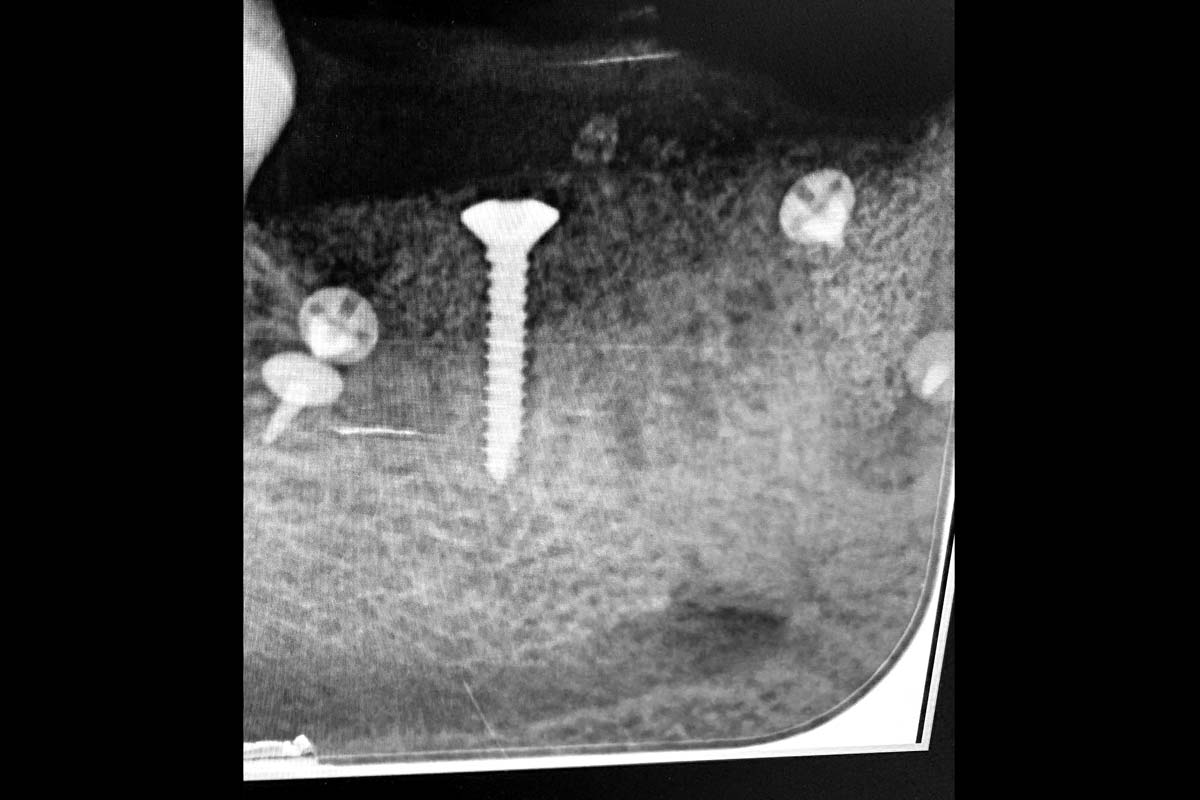

02/29 - Based on the intraoral x-ray a vertical bone defect of about 4 mm extending from 4.6 to 4.4 was determinedVertical bone augmentation and broadening of attached gingiva using cerabone®, permamem® and mucoderm® - Dr. R. Naimoli